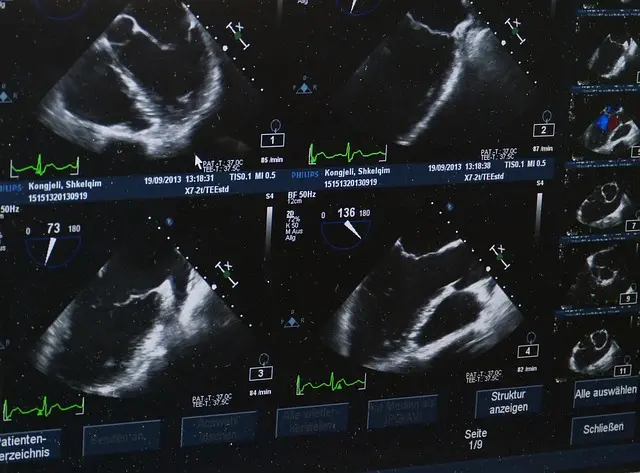

22 de julho de 2019Categorias Exames de Imagem MEDICINA DIAGNÓSTICA SAÚDE DA MULHER ultrassonografiaUltrassom: conceito, com doppler, tipos. Pra gravidez, na gravidez.Investigação interna do corpo. As facilidades e benefícios do ultrassom. A ultrassonografia – ou ecografia – é uma técnica da medicina de diagnóstico por imagem que […]